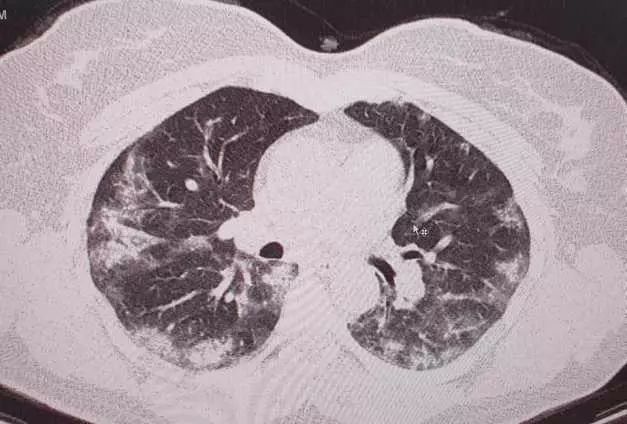

"Forme atipice de Covid-19. Toţi medicii care se confruntă cu patologia Covid-19 ar trebui să se gândească la această boală şi în cazul unui pacient cu simptome "ciudate" apărute în plină stare de sănătate! Unii mă vor întreba ce înţeleg prin simptome ciudate! Medicii înteleg ce spun! Astăzi am depistat un caz de Covid 19 la o pacientă relativ tânără, fără febră, fără tuse... fără niciun simptom considerat tipic sau sugestiv pentru Covid-19! Faptul ca am folosit ecografia pulmonară ce mi-a relevat modificări sugestive, m-a convins de necesitatea unui examen CT pulmonar. Examinarea tomografică a fost concludentă. Ulterior, a urmat şi confirmarea serologică. Simptomele pacientei erau doar astenie marcată, ameţeli, somnolenţă. Saturaţia in oxigen 98%! Fără comorbidităţi!", a scris medicul, pe contul personal, postând și mai multe fotografii cu plămânii pacientei.

"Opacităţi "în sticla mată" dispuse la periferia plămânilor...foarte concludente...", a scris dr. Alexandru Andriţoiu, în dreptul imaginii.